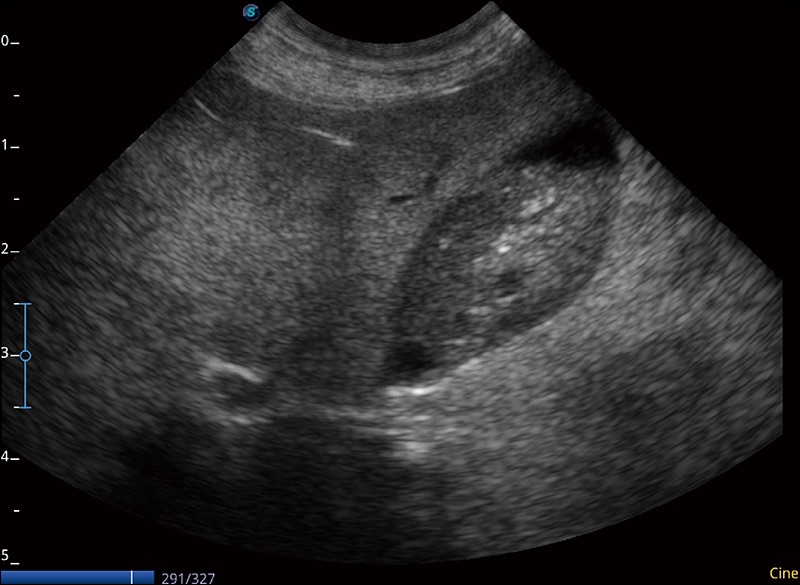

α1卓越的图像质量和便捷的工作流程,使每位宠物医生都能轻松扫查。其全面的兽用应用功能和紧凑型的结构设计,可以满足动物检查的多种需要。专业的预设检查模式和多领域测量软件包有助于为不同类型的动物提供检查, 让宠物医生能够出色的完成工作。

任意波束合成技术

在不牺牲时间分辨率的情况下提供出色的图像

空间复合成像

优化不同角度的图像

扩展成像

支持线阵和凸阵探头,一键操作即可获得更宽的图像视野

实时宽景成像

可实时观察感兴趣区域和病变位置